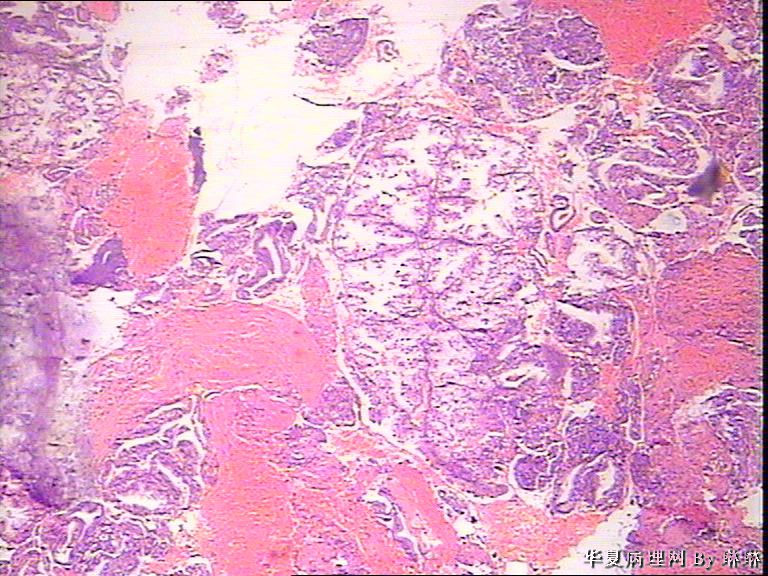

患者女性,38岁,月经量多4个月,曾服用止血药物,无其他病史。

• 子宫内膜,请教图4

图4

腺体呈高度分泌反应,我们必须结合病史,考虑是否药源性反应,或持续黄体期子宫内膜.

晚泌期宫内膜,并见A-S现象

开始临床没有提供怀孕的病史,后来我们有咨询临床科室,大夫还是说没有用药、月经正常,刚过了经期,月经量多,这次月经持续时间长入院。所以我们开始排除了高度分泌的A-S反应,看到腺体增生呈乳头状,还有异型性,而且镜下部分子宫内膜还有增生期改变的,不完全是高度分泌的。再三考虑后还是要求临床查了血HCG,结果显示HCG370多。最后我们发了单纯性增生伴高度分泌。